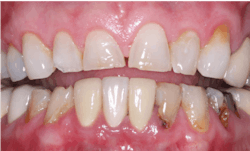

- Zirconia with stains placed on the presintered ceramic and fired into the restorations: Currently only offered by select labs; this material is looking promising (figure 2)